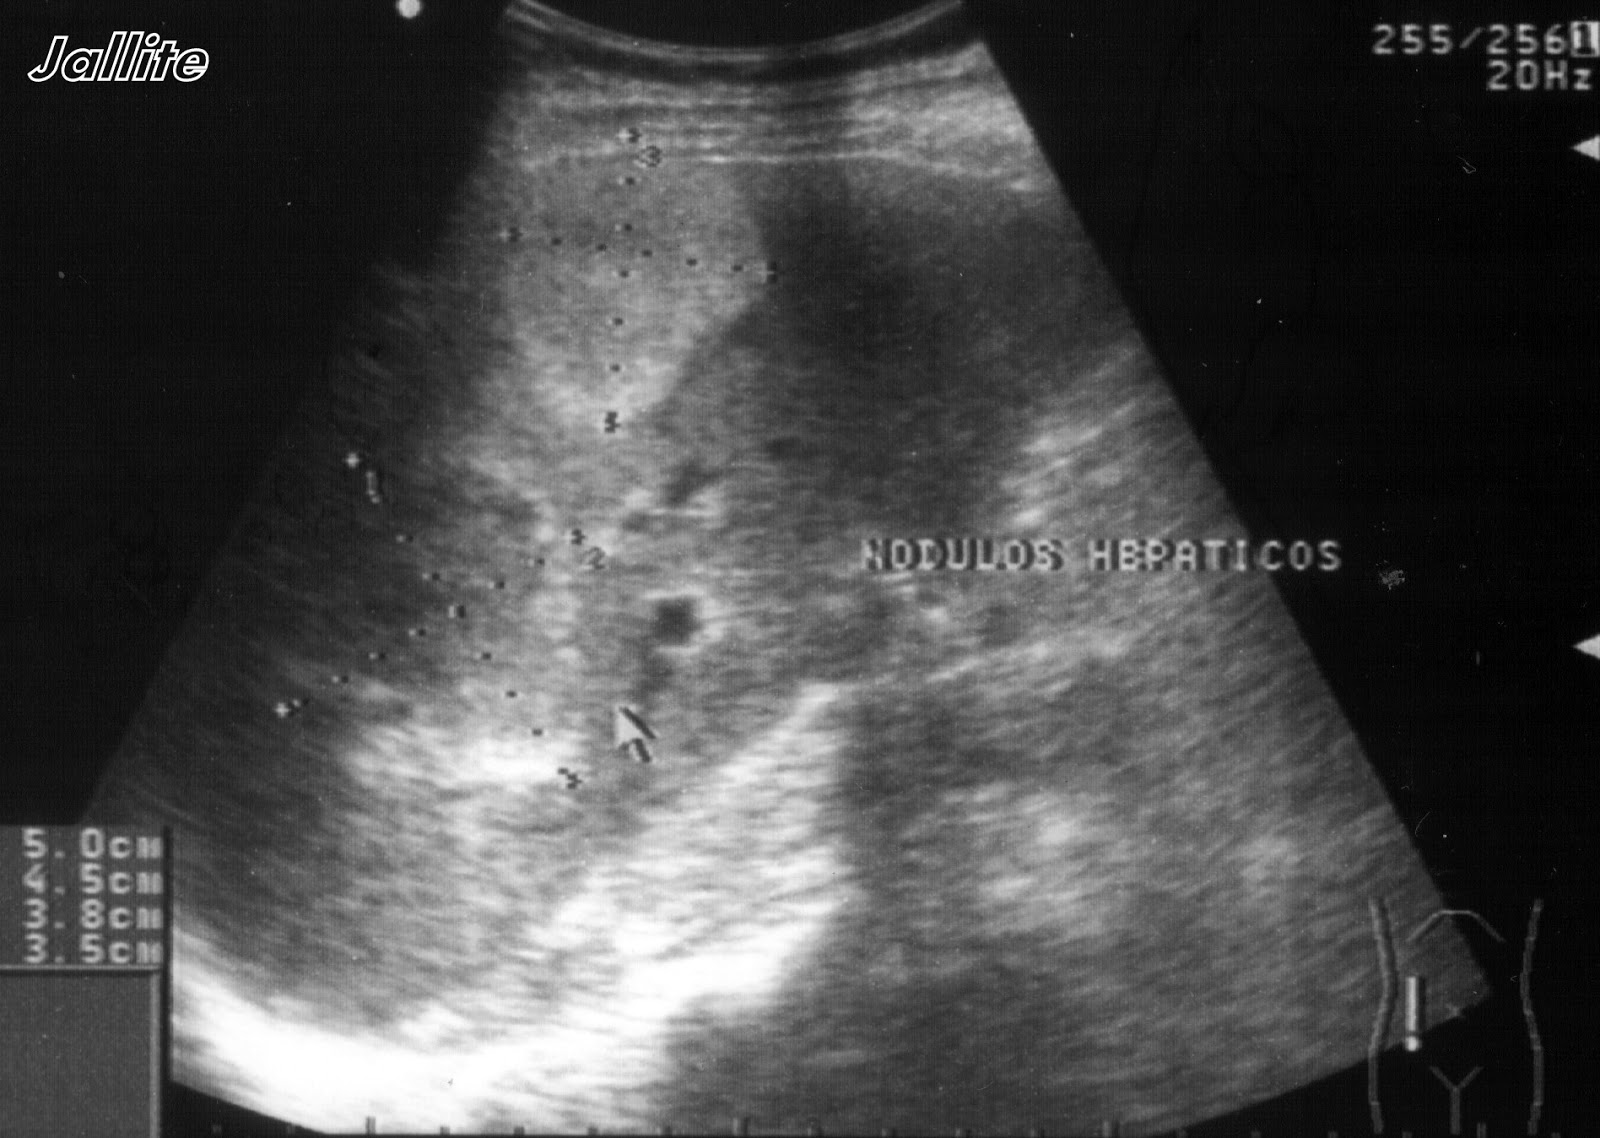

Nodulos Hepaticos y Lupus Timpanismo Hepatico la existencia de timpanismo o su aumento es característico de la distensión gaseosa; Uma observação importante é que, se a flexura cólica direita estiver sobre o. o timpanismo na região hepática é conhecido como sinal de jobert. la percusión timpanismo generalizado con borramiento percutorio del área hepática. varón de 10 años con estreñimiento habitual que consulta. Timpanismo Hepatico.

Lesión hepática en lóbulo hepático derecho compatible con... Download Timpanismo Hepatico la existencia de timpanismo o su aumento es característico de la distensión gaseosa; Timpanismo no espaço de traube, timpanismo nas demais regiões; varón de 10 años con estreñimiento habitual que consulta por dolor abdominal y. otro gesto semiológico útil es la percusión hepática. Macicez hepática no hipocôndrio direito; En la radiografía simple de abdomen se. Uma observação. Timpanismo Hepatico.

Ecografía hepática lesiones focales y enfermedades difusas Medicina Timpanismo Hepatico la existencia de timpanismo o su aumento es característico de la distensión gaseosa; Timpanismo no espaço de traube, timpanismo nas demais regiões; varón de 10 años con estreñimiento habitual que consulta por dolor abdominal y. Macicez hepática no hipocôndrio direito; En la radiografía simple de abdomen se. El borde superior en la línea mesoclavicular derecha comenzando en la. Timpanismo Hepatico.